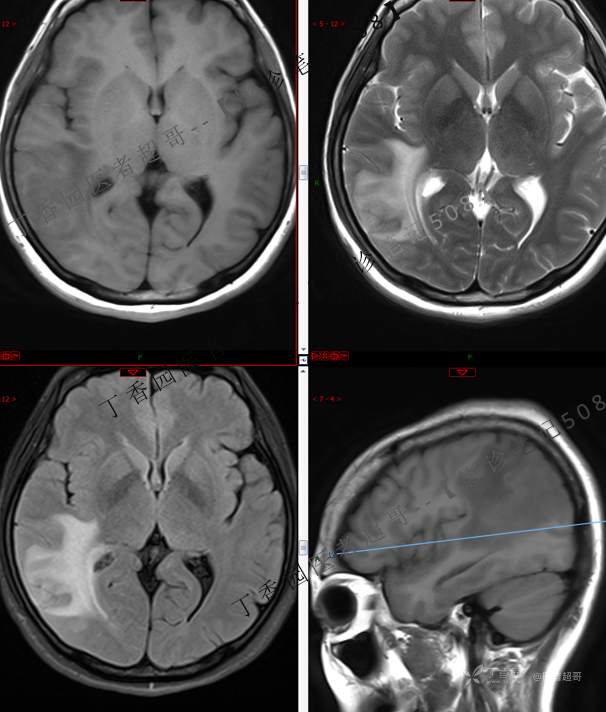

【影诊笔记508】同病异影,个人感觉有难度,欢迎分析,领丁当!有详细术程及病理!

患者性别:女

患者年龄:46岁

主 诉:突发一过性意识不清伴肢体抽搐5天余。

现病史:患者5天余前无明显原因及诱因出现一过性意识不清,伴肢体抽搐,持续约2-3分钟,后意识逐渐恢复,无明显头痛头晕,无恶心呕吐,无肢体抽搐,无呼吸困难,无二便失禁,后就诊于当地医院,行颅脑CT示“颅内占位性病变”,予以药物对症治疗,具体不详,门诊以“颅内占位性病变”,收入我科。患者自发病以来,未进饮食,近期体重无明显变化。